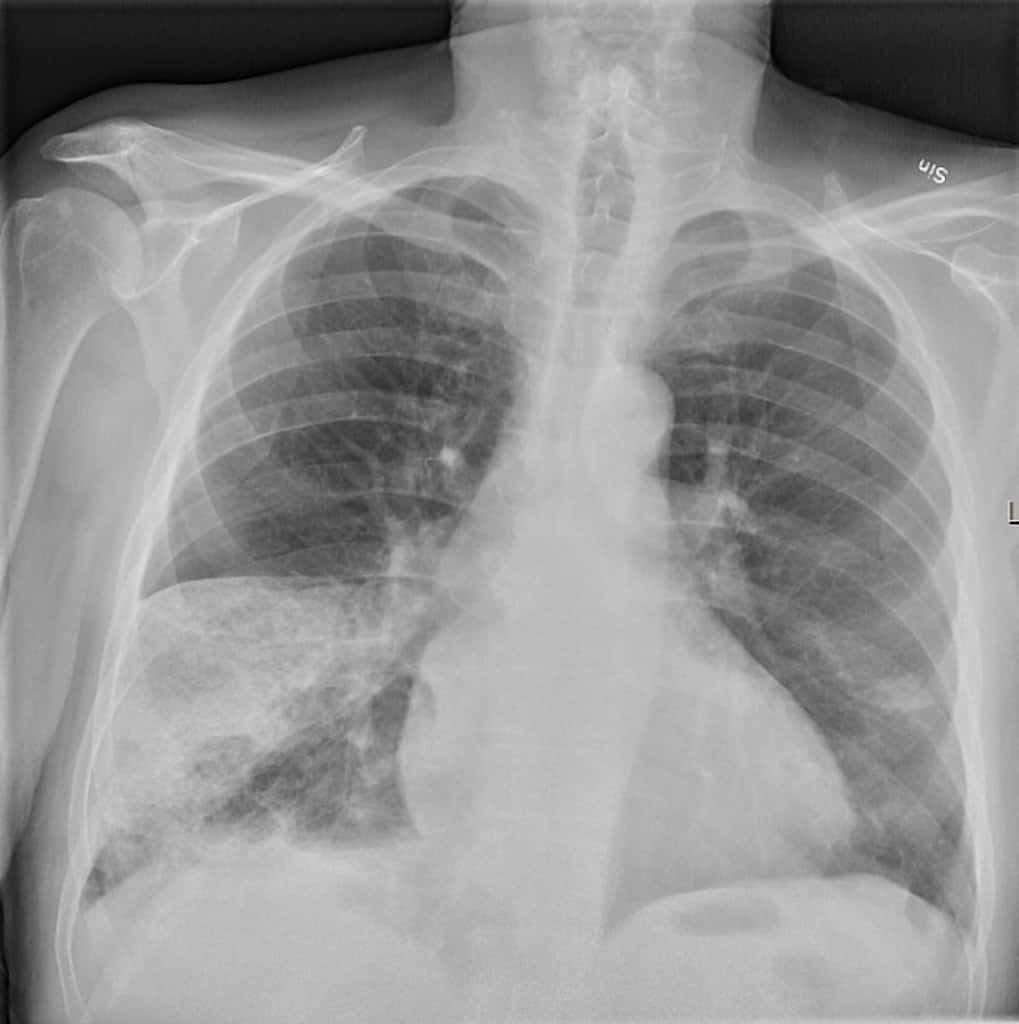

[Figure, AP Chest xray, Right pulmonary...] StatPearls NCBI Bookshelf Chest X Ray Pe Chest radiography is neither sensitive nor specific for a pulmonary embolism. There are several described signs of pulmonary embolus on chest radiography which are suggestive of this diagnosis. Here we summarize the 2019 esc guidelines for the diagnosis and management of acute pe, which were developed in collaboration. It is used to assess differential diagnostic possibilities such as pneumonia and. Chest X Ray Pe.

Westermark’s and Palla’s Signs in Acute Pulmonary Embolism Circulation Chest X Ray Pe There are several described signs of pulmonary embolus on chest radiography which are suggestive of this diagnosis. Here we summarize the 2019 esc guidelines for the diagnosis and management of acute pe, which were developed in collaboration. It is used to assess differential diagnostic possibilities such as pneumonia and pneumothorax rather than. Chest radiography is neither sensitive nor specific for. Chest X Ray Pe.

Radiographic features of pulmonary embolism Hampton's hump Chest X Ray Pe It is used to assess differential diagnostic possibilities such as pneumonia and pneumothorax rather than. Chest radiography is neither sensitive nor specific for a pulmonary embolism. There are several described signs of pulmonary embolus on chest radiography which are suggestive of this diagnosis. Here we summarize the 2019 esc guidelines for the diagnosis and management of acute pe, which were. Chest X Ray Pe.

Chest xray of patient with suspected pulmonary embolism (PE) Chest X Ray Pe It is used to assess differential diagnostic possibilities such as pneumonia and pneumothorax rather than. There are several described signs of pulmonary embolus on chest radiography which are suggestive of this diagnosis. Here we summarize the 2019 esc guidelines for the diagnosis and management of acute pe, which were developed in collaboration. Chest radiography is neither sensitive nor specific for. Chest X Ray Pe.